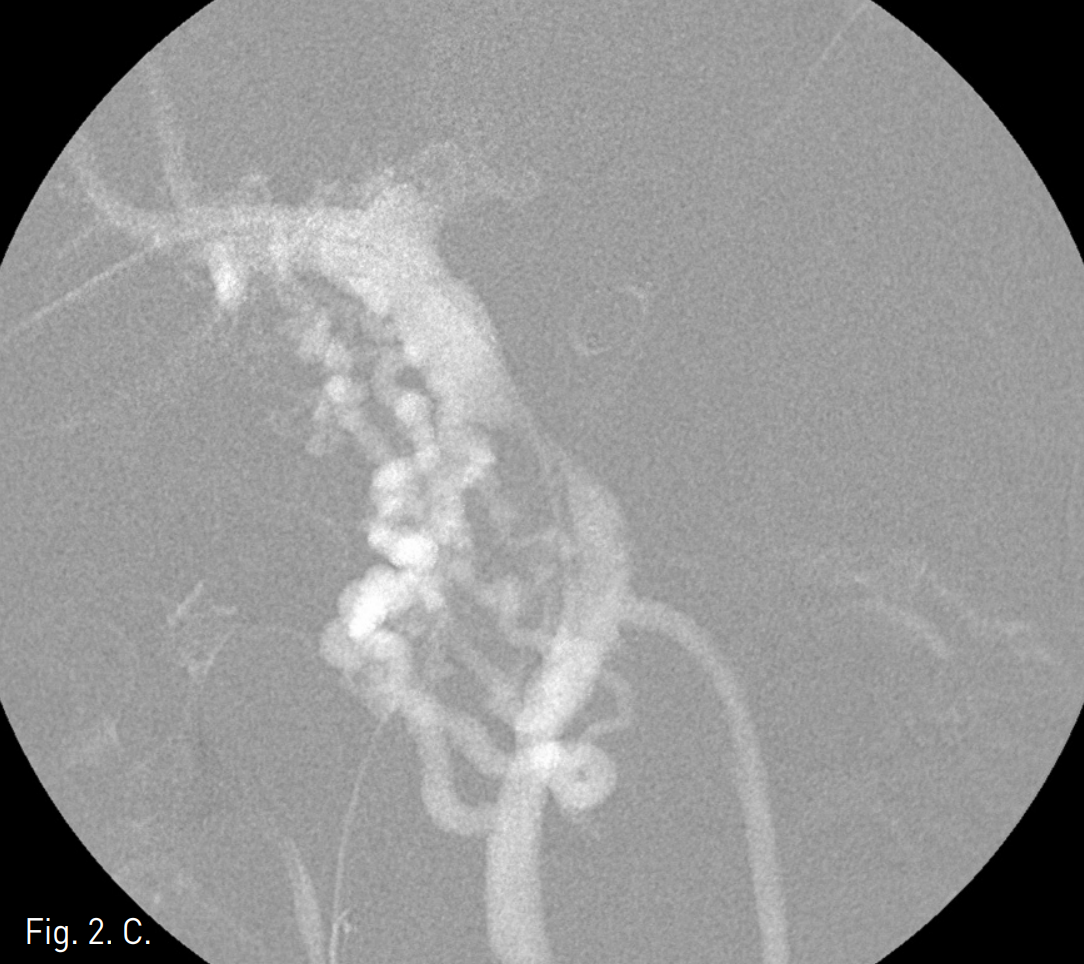

주문맥의 협착부위에서 10mm x 4cm balloon catheter (Synergy, Boston Scientific, Natick, Mass)를 사용하여 풍선확장술을 시행하였으나 elastic recoil로 인하여 반응이 없었음(Fig 2B-C). 자가팽창스텐트(14mm, 6cm, Zilver, Cook, USA)를 협착부위에 설치하고 10mm x 4cm balloon(Synergy, Boston Scientific, Natick, Mass)을 이용하여 post-stent balloon dilatation을 시행함. (Fig 2D)Stent 설치 후 협착 근위부와 원위부의 압력차는 1mmHg (SMV는 18mmHg, 주간문맥은 17mmHg)로 감소되었음(Fig 2E).

Fig. 2

C. After balloon dilatation, portal vein stenosis is still present.